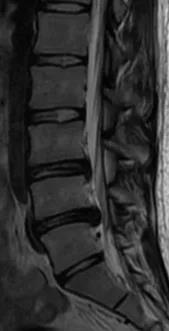

术前MRI可见L4/5突出髓核